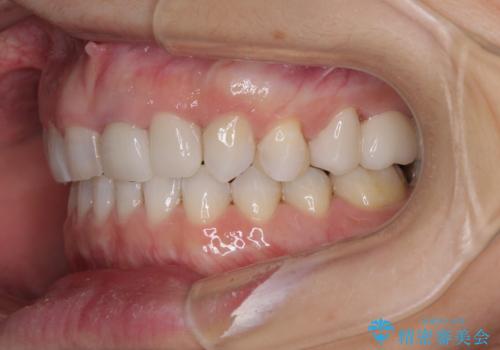

咬み合わせ改善のため、前歯の過剰歯を抜去し、ワイヤー矯正にて歯列と咬み合わせることとしました。

左上の奥歯のブリッジや前歯のセラミッククラウンはいったん除去し、矯正治療後に補綴治療を行うこととしました。

また、右下の抜歯が必要な奥歯は、矯正治療の途中でインプラントを埋入し、矯正治療後に上顎と合わせて補綴治療を行うこととしました。

上下非接触の咬み合わせは、舌突出癖によるところが大きく、トレーニングを行いながら治療を進めていきました。